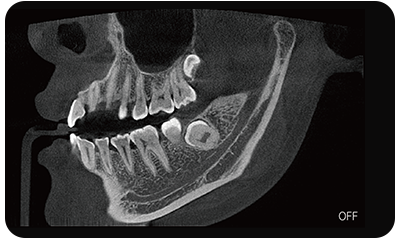

采用高性能CMOS探测器,最大FOV可达16x9cm星垂视野并支持无极可调,最小体素0.05mm。头颅采集模式,支持3s超快速扫描,最小像素99um,保证优质影像快速采集。

可根据临床需求任意调整成像区域大小实现局部超清三维显示

临床样片